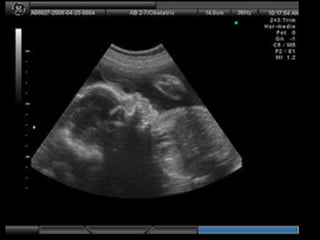

Este documento describe brevemente la historia de la radiografía y los rayos X, y explica que existen diferentes tipos de radiografías y aplicaciones en odontología, incluyendo radiografías intraorales y extraorales. También proporciona ejemplos de actividades para identificar estructuras que aparecen en radiografías dentales de acuerdo a su radioopacidad.